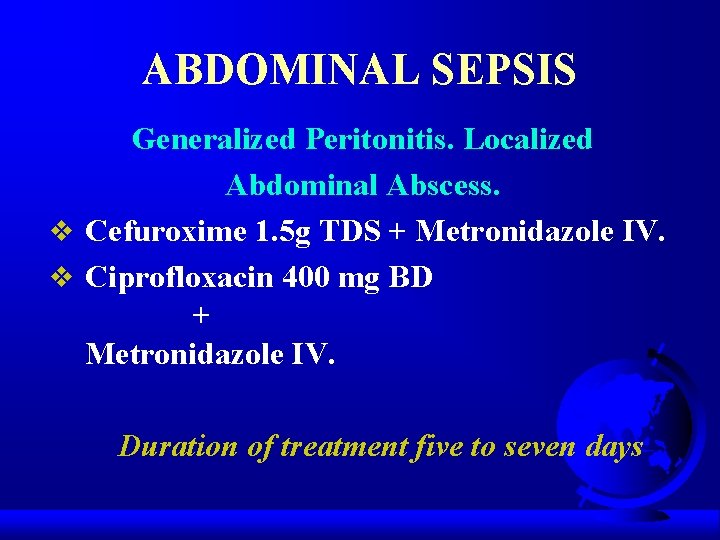

sepsis abdominal Symptoms specific to the type of infection, such as painful urination from a urinary tract infection or worsening cough from pneumonia. Why does abdominal sepsis occur? Abdominal sepsis represents the host’s systemic. Overview an infection can start with a simple injury—like a shallow cut on the arm—that allows bacteria and other microbes to slip into your body’s tissue or circulation. Severe sepsis and septic shock; Without urgent treatment, it can lead to. What causes abdominal pain in sepsis? Although sepsis is a systemic process, the pathophysiological cascade of events may vary from region to region.

Sepsis intra abdominal

Sepsis intra abdominal

Sepsis abdominal fisiopatología, diagnóstico y tratamiento Medcmc

Sepsis intra abdominal

Sepsis intra abdominal